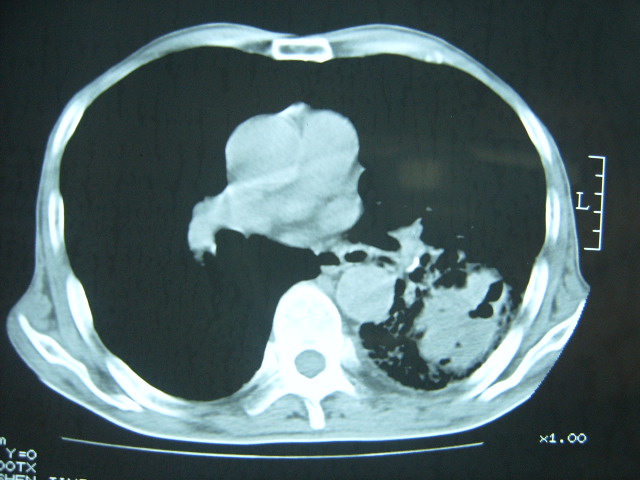

男74岁,咳嗽,寒战,低烧。有糖尿病史。

考虑:1、左下肺脓肿;

2、双肺结核。

考虑:糖尿病合并:1、左下肺炎继发肺脓肿;

两肺结核,左下肺大片实变,内见空洞性病变,壁不规则,结合糖尿病史,考虑:结核性?霉菌性?建议结合实验室检查或治疗后复查。